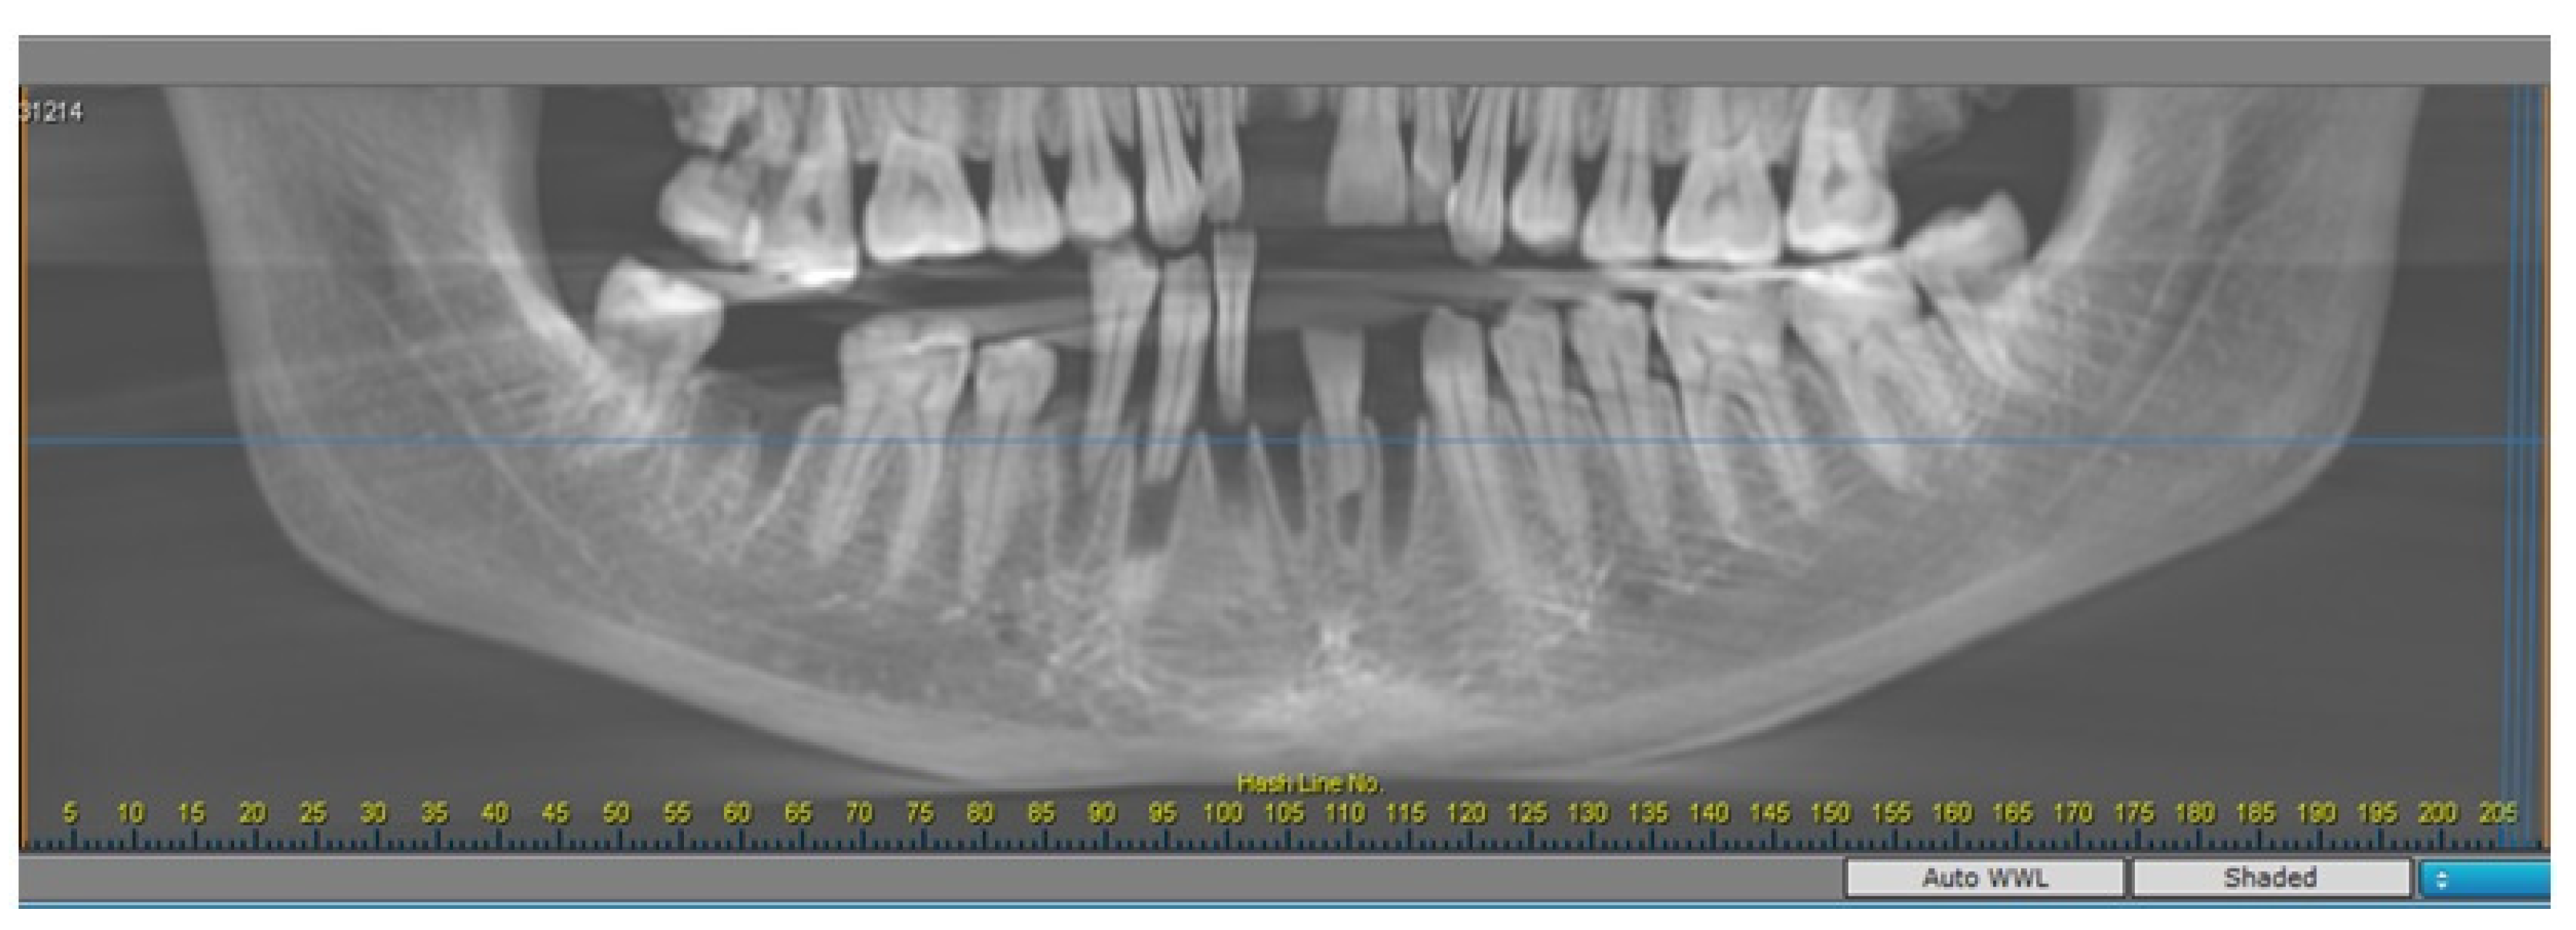

2.2. Radiomorphometric Assessments